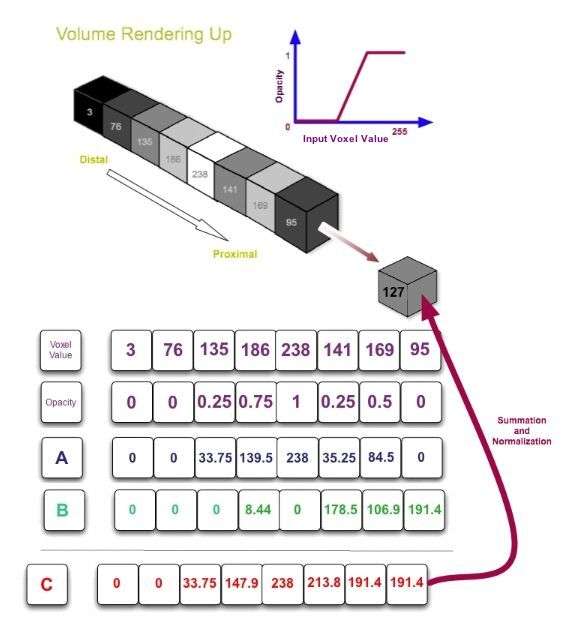

Volume rendered projections are shown in the first two images along the bottom row of our collection of example axial projections. This image compositing method involves applying an opacity function to the voxel data as well as a recursive addition of the resulting data. An equation of the form:

where

- An = (α).(Voxel Value of voxel, n),

- Bn = (1-α).(Voxel Value of voxel, n-1), and

- α = opacity, in the range 0 (i.e. fully transparent) to 1 (i.e. fully opaque),

is applied to each line of voxels as illustrated in the following figure:

The figure shows the line of voxels we've used previously with an opacity table in the top right corner. The opacity function shown is one where a zero opacity is applied to voxel values below a threshold level, a linear increase in opacity is applied to an intermediate range of voxel values and maximum opacity applied to high voxel values. The opacity table is somewhat like the look-up table used for greyscale windowing which we've described earlier, with the function applied to the opacity of voxel values instead of to their grey levels. Note that more complex opacity tables to the one used in our figure above can be also applied, e.g. logarithmic and exponential functions.

The bottom half of the figure shows the steps involved in calculating the volume rendered value of the composited voxel. Voxel values are shown on the top row with opacity values, derived from a crude opacity table, for each voxel shown on the second row. The third, fourth and fifth rows detail the values of A, B and C, calculated using our volume rendering equation above. The final voxel value is obtained by summing the bottom row, and normalizing the result to, say, a 256 level grey scale.

The outcome of this form of processing is the generation of an image which includes visual depth cues on the basis that similar voxel values will be displayed with a similar transparency and those closest to the reference slice having a stronger contribution than those from more distal slices. Further, note that all voxel values in each line contribute to the rendered image, in contrast to the limited number of voxels that contribute to a MIP or a MinIP image. A 3D effect results from volume rendering, as illustrated in the images above.

Notice that volume rendering can be applied from distal to proximal slices, as illustrated in our figure, as well as in the opposite direction, i.e. from proximal to distal slices. Hence the terms Volume Rendering Up and Volume Rendering Down used in our set of nine example images above.